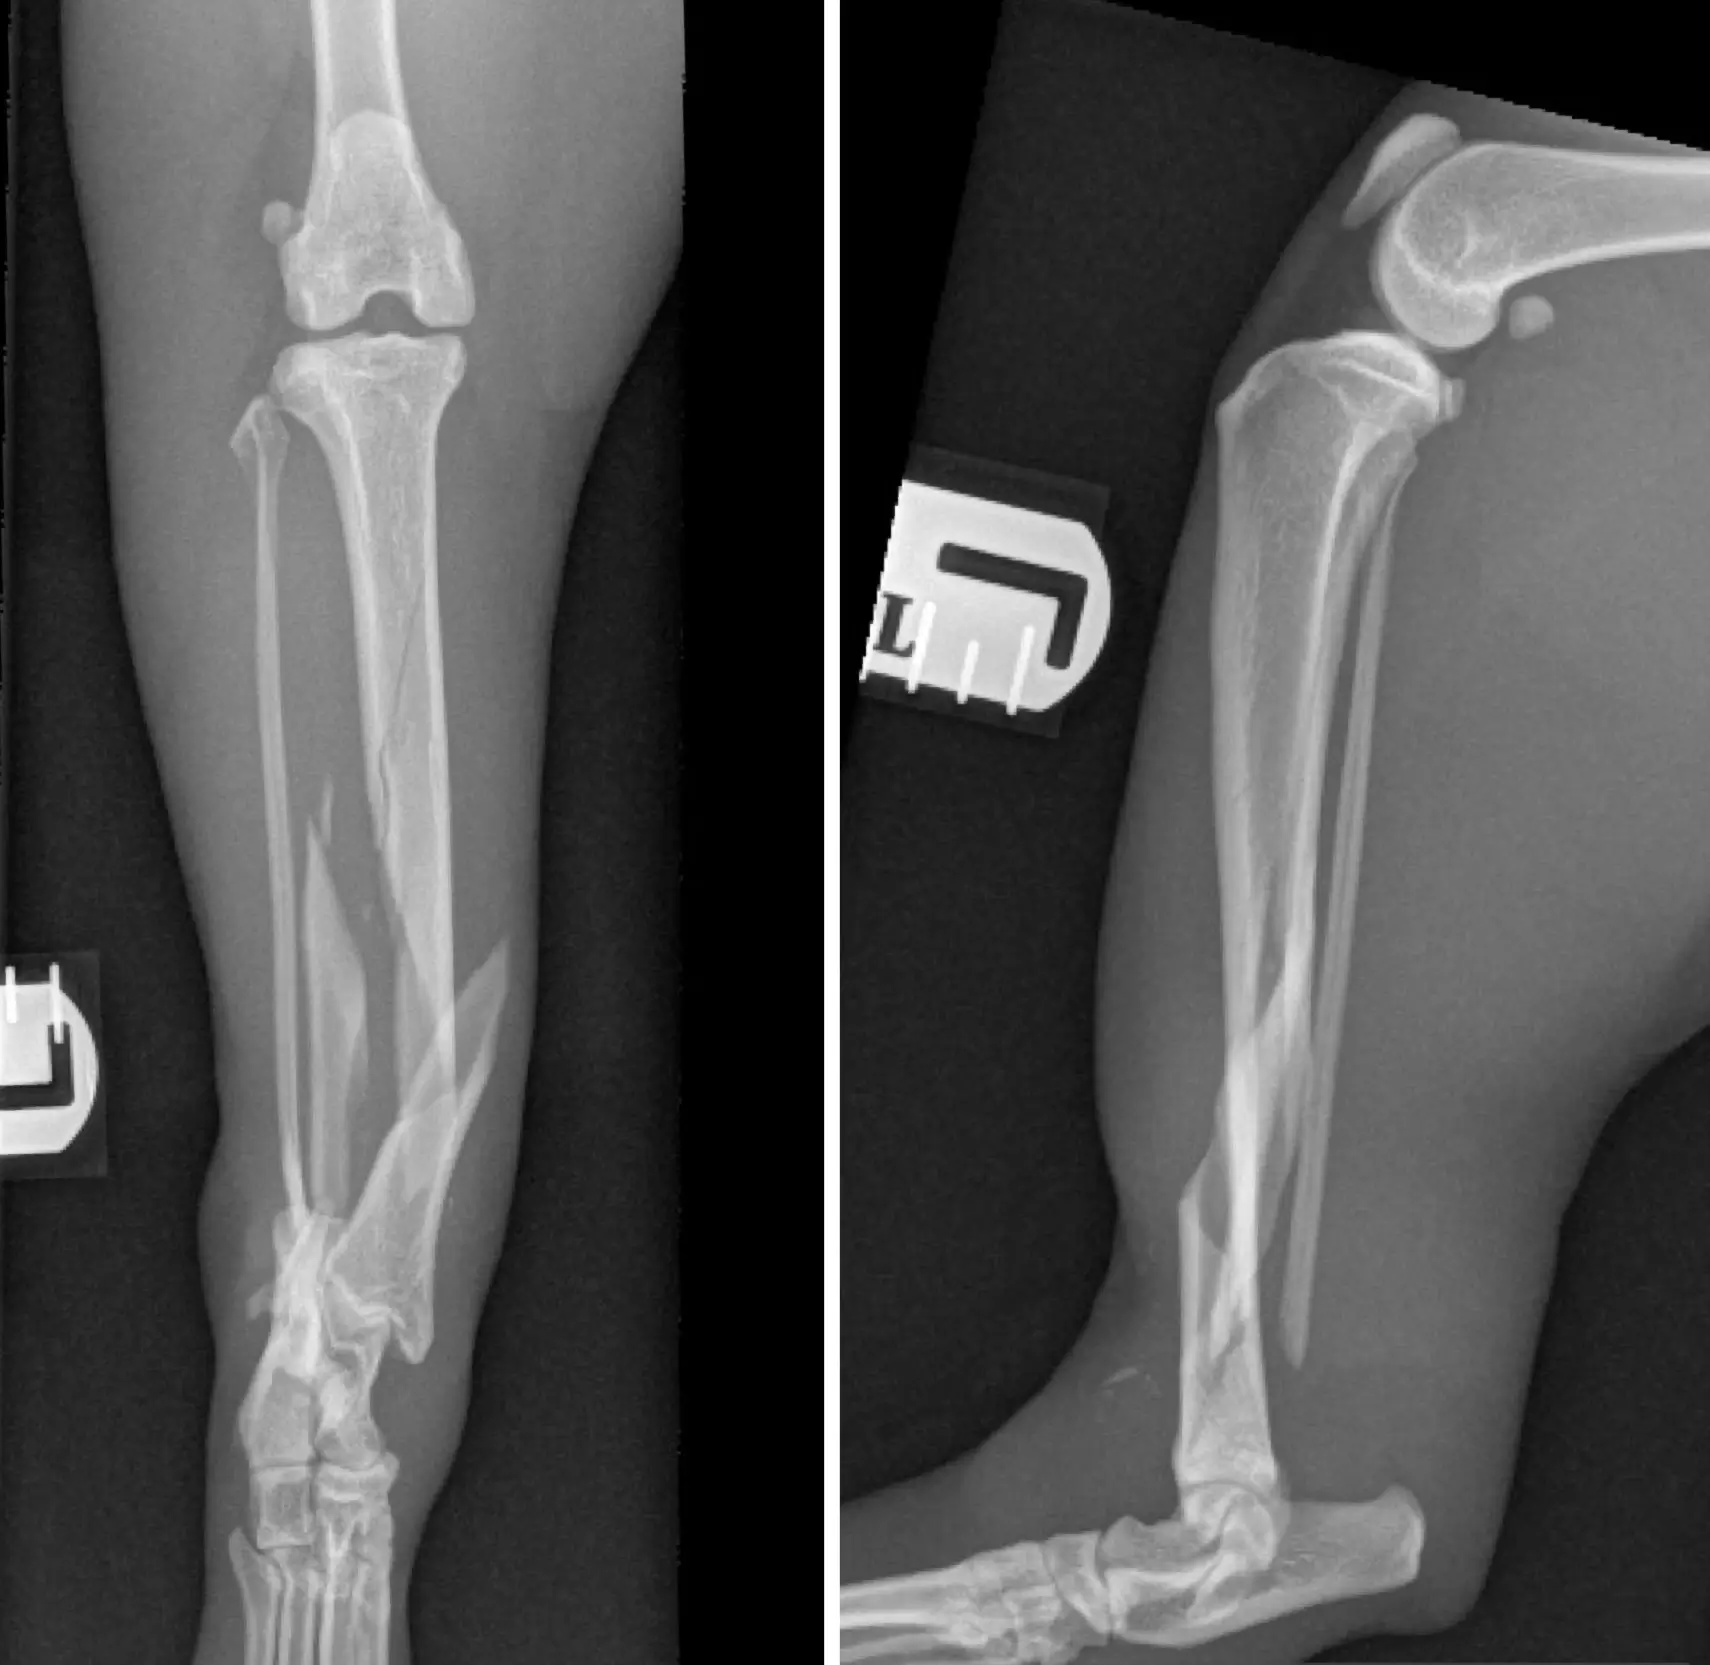

X-Ray

• Fractures

• Trauma

• Digital radiography (X-rays) for fast and accurate assessment of musculoskeletal, pulmonary, gastrointestinal, and urogenital disorders.